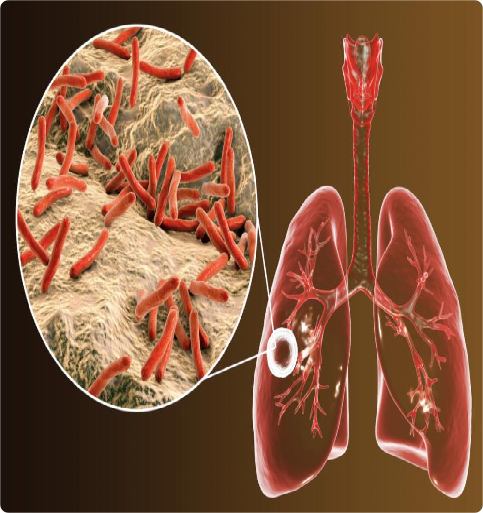

一、什么是结核病

结核病是由结核分枝杆菌引起的慢性传染病,主要通过呼吸道飞沫传播,最常见的患病部位是肺,称为肺结核。结核病的临床表现多种多样,肺结核会引起咳嗽、咳痰、咳血、乏力、消瘦、胸痛、午后低热、夜间出汗、食欲减退、月经不调、闭经等,严重时甚至危及生命;还可能累及全身损伤,如累及骨骼引起疼痛、甚至瘫痪,累及大脑引起头痛、呕吐、意识障碍等。易感人群为免疫力低下及营养不良人群。